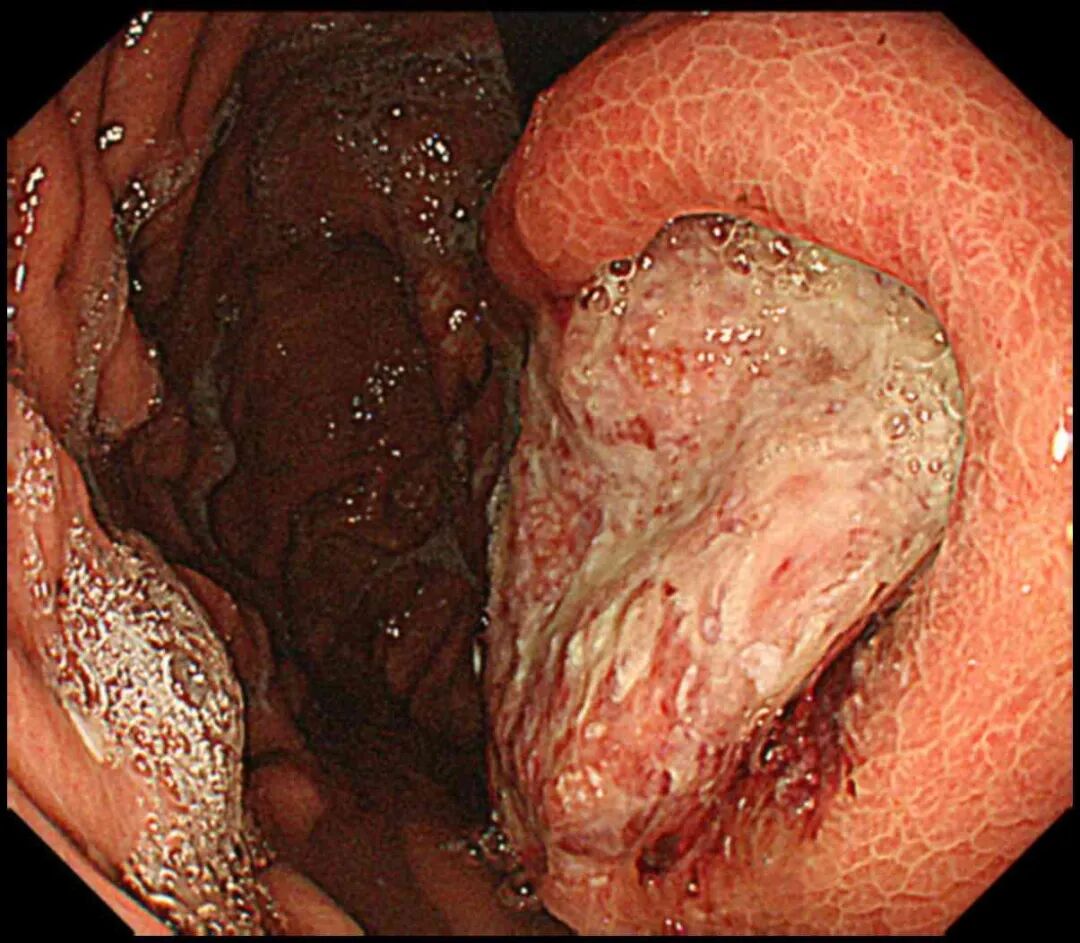

当你还沉浸在饮酒后的欢愉时,高浓度酒精对胃黏膜的严重伤害已经开始了。

与药物更多引起局部溃疡不同,酒精的伤害可能更为广泛。胃里的大片黏膜糜烂出血,让你出现腹痛、呕血、黑便。

一顿大酒,有时就要以急诊室结尾了。

药物、酒精对胃黏膜的伤害,会切实在胃上留下痕迹,让你的痛苦持续。不要喝酒,不要滥用药物,按照医嘱使用必要的胃药保护。